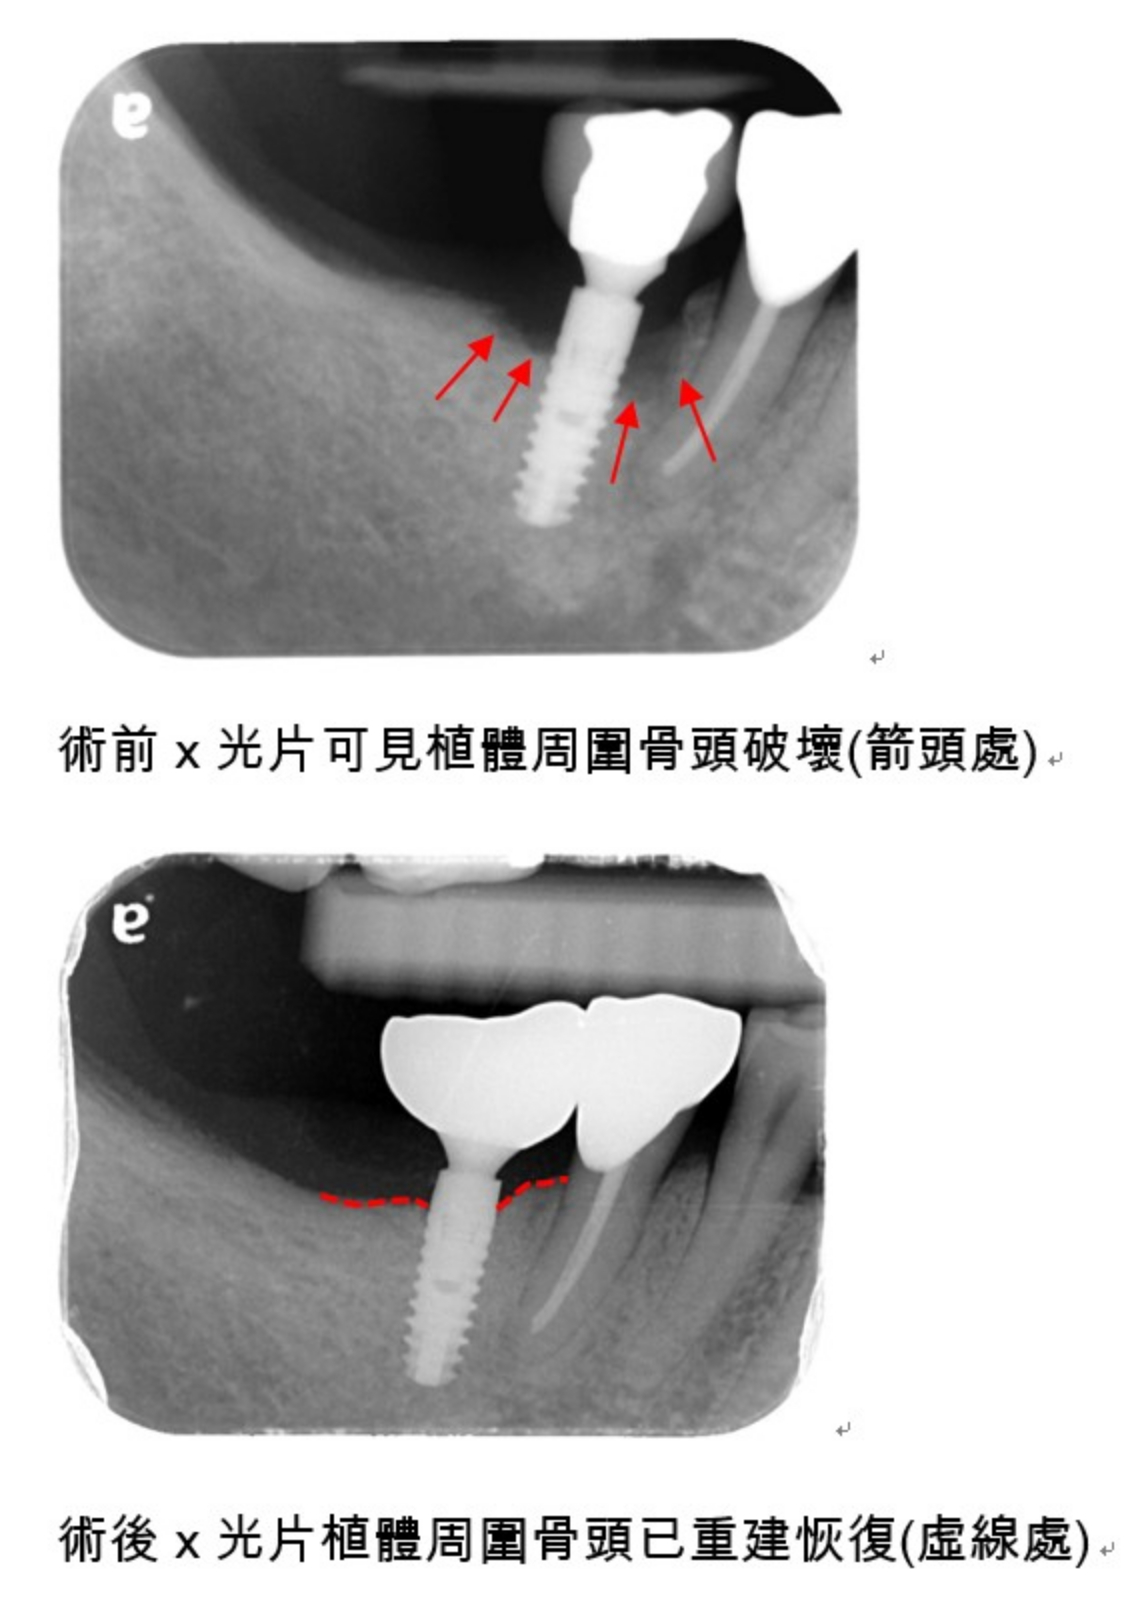

治療植體周圍疾病可分為非手術性治療與手術性治療,非手術性治療包括機械式清創、抗生素殺菌治療或是雷射治療。而手術性治療包含了植體表面清創、去感染與去毒性化,利用骨粉與再生膜進行引導骨再生術重建植體周圍先前被破壞的骨頭,有時後還會適度地搭配移除植體表面螺紋來達到光滑表面,減少細菌堆積與術後維護期間較容易的清潔。然而,當植體周圍骨頭破壞較為嚴重時,無法或不易以補骨重建時,移除受感染的植體,亦是治療的選項。